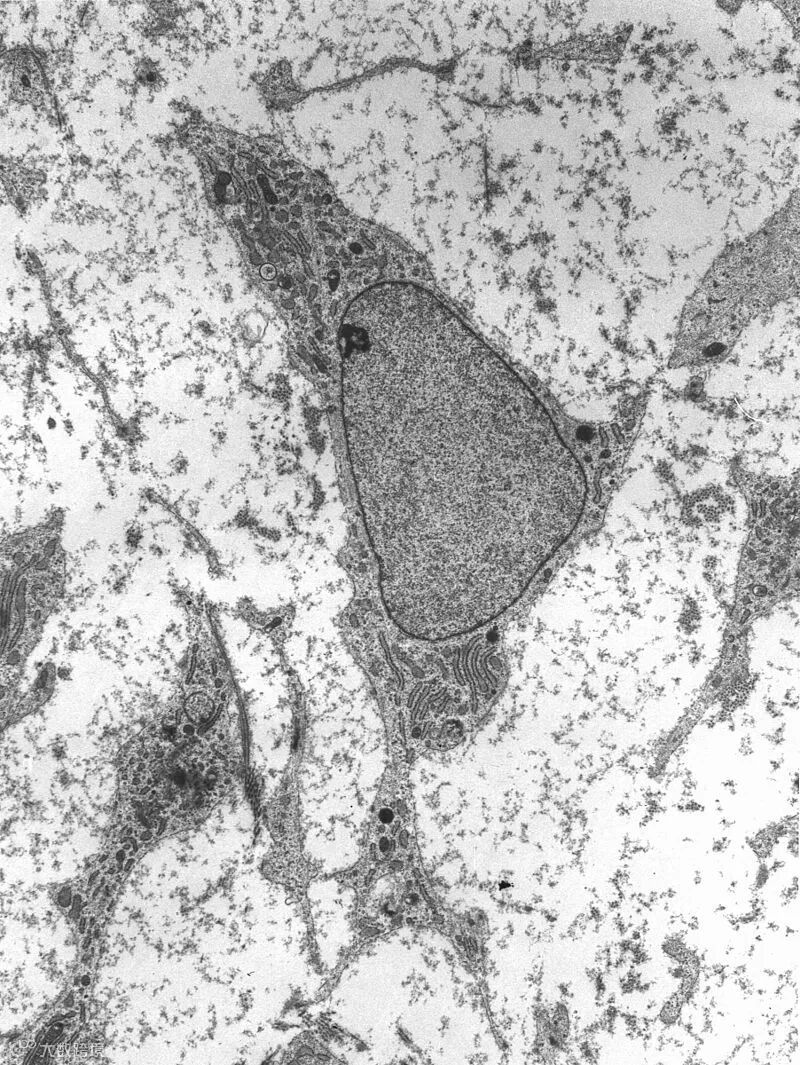

专能干细胞的微环境能让组织中的干细胞保持长久的自我更新功能,对于它们执行正常的功能有着关键的作用。目前,已经找到了不少案例,涵盖肝脏干细胞、骨髓干细胞、以及种系干细胞、上皮干细胞、神经干细胞等类型。在对这些案例进行分析后,科学家们发现,尽管涉及到细胞种类有所不同,但这些微环境却有许多相似之处。

具体来说,一个典型的干细胞微环境会包括细胞、细胞外基质、以及可溶性因子(如生长因子)。一般而言,这些适合干细胞的微环境深植于组织内部,以维持特定的氧气、离子、生长因子、细胞因子、以及趋化因子的梯度。

▲干细胞的分化受到了细胞外基质的影响

科学家们发现,细胞与细胞外基质的相互作用,是干细胞潜力的重要调节与决定因素。不少干细胞位于细胞外基质之中,而后者往往就是干细胞与其子细胞的产物。这些基质由大量分泌蛋白组成,与细胞之间动态互动。人们发现,不同组织或器官的基质有不同的结构特征,往往由其功能所决定。比如对于心脏这一在发育过程中最早获得功能的器官来说,一系列特殊的细胞类型必须在基质中汇集,以配合泵血功能。而在骨骼组织中,基质中的分子则会提供结构上的支持。

而干细胞的分化也会受到基质的影响。基质通过维持其结构的完整性,来维持干细胞的身份,并对它们的激活进行调节。举例来说,细胞外基质刚性的不同,能影响到骨髓干细胞的增殖、迁移、以及分化。此外,除了细胞外基质本身,位于基质中的生长因子和糖蛋白对于干细胞也有重要的调节作用。